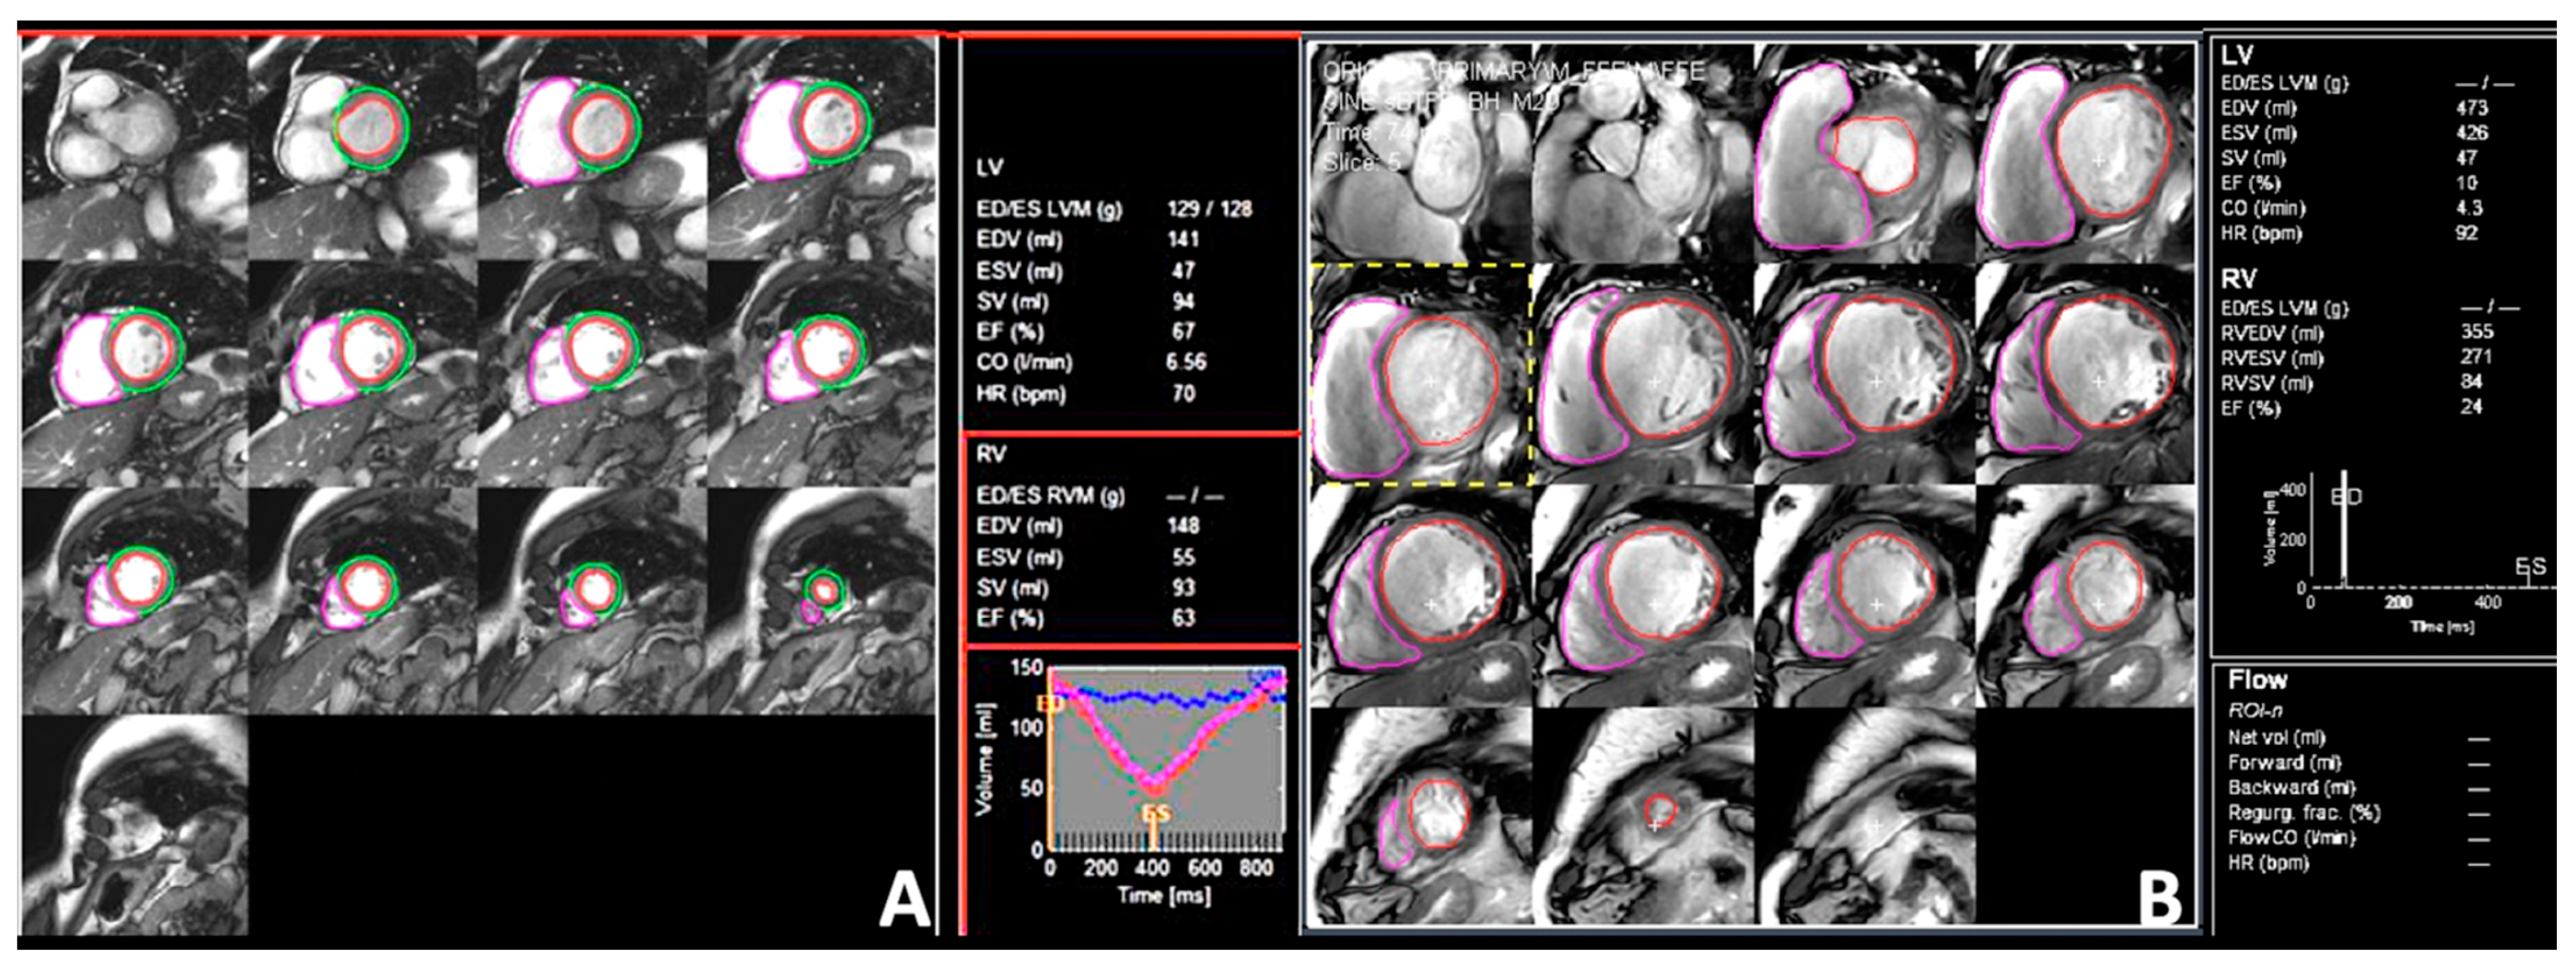

4.2. Cardiac Magnetic Resonance